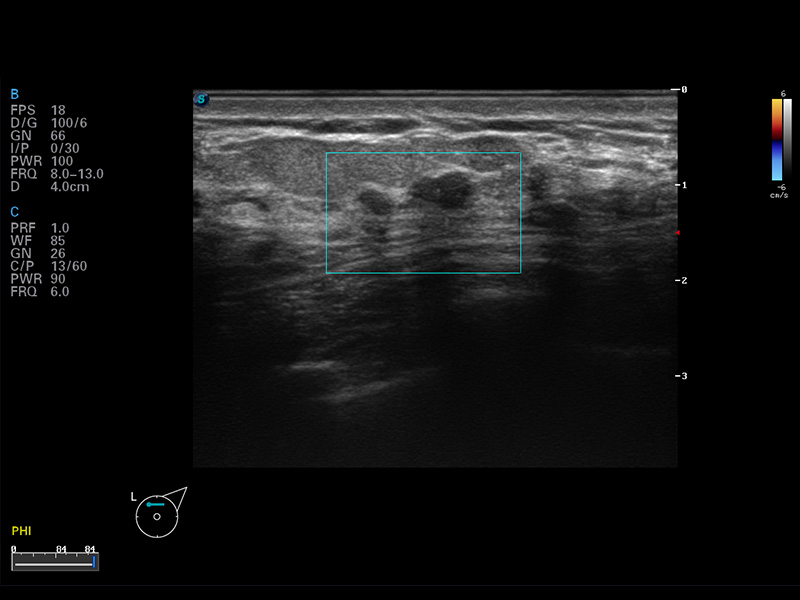

S8 EXP便攜式彩色多普勒超聲診斷儀是開立醫(yī)療研發(fā)的高端全身應(yīng)用型便攜彩超。高通道的VIS平臺融合可視化(Visual)、智能化(Intelligent)和人性化(Smart)的特點,配以開立醫(yī)療自主研發(fā)生產(chǎn)的探頭大家族,使您能夠快速、準(zhǔn)確的獲得病人信息,提高工作效率的同時減輕疲勞。

成像技術(shù)

μ-Scan微米成像

諧波成像

空間復(fù)合成像